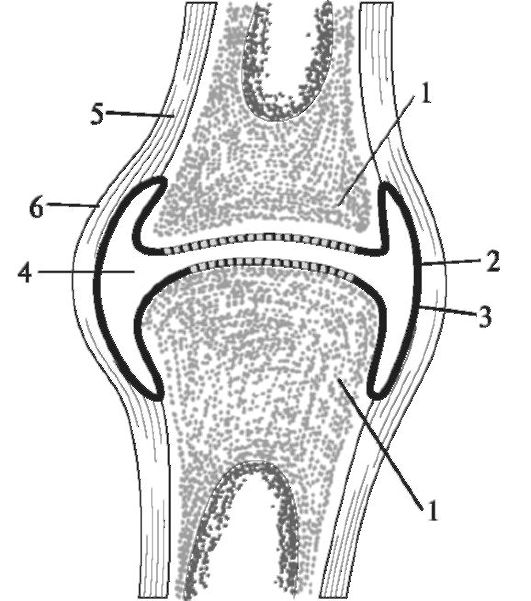

Рисунки Суставов: Анатомические Иллюстрации